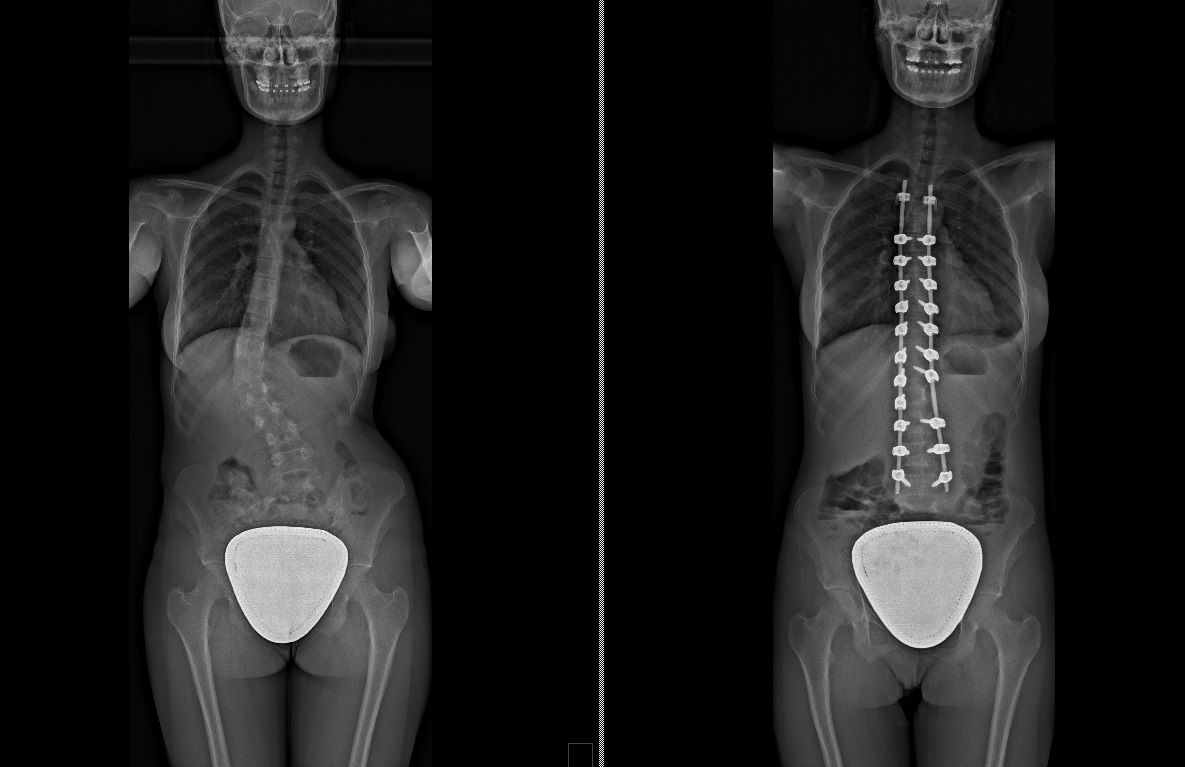

Laureato in Medicina e Chirurgia presso l'Università degli Studi di Napoli Federico II nel 2011, Specializzato in Ortopedia e Traumatologia presso la stessa Università nel 2017. Da subito ho dedicato i miei studi all'ambito della chirurgia vertebrale e della neurochirurgia. Infatti ho frequentato per 9 mesi tra il 2015 ed il 2016 i reparti di Neurochirurgia dell'IRCCS Neuromed di Pozzilli (IS) per apprendere le tecniche di trattamento delle Patologie della Colonna Vertebrale. Da allora il mio principale interesse è rivolto al trattamento conservativo e, dove necessario, chirurgico delle deformità della colonna vertebrale, sia dell’età dell’accrescimento che degenerative dell’adulto: scoliosi, dorso curvo, spondilolisi, spondilolistesi. Ulteriori campi di interesse sono il trattamento di lombalgia e lombosciatalgia, ernia del disco, stenosi del canale vertebrale, fratture vertebrali traumatiche o da osteoporosi (vertebroplastica), terapia del dolore osteoarticolare mediante tecniche mininvasive (radiofrequenze). Dal 2017 sono Consulente presso IRCCS Neuromed di Pozzilli (IS) con incarico di Responsabile del Centro per la Diagnosi e Cura delle Deformità Vertebrali e Scoliosi, dove svolgo la mia attività chirurgica in regime di convenzione. Svolgo la mia attività chirurgica in regime di solvenza e di convenzione assicurati presso la Clinica Ruesch di Napoli. Continuo costantemente la mia formazione con esperienze di perfezionamento nazionali ed internazionali. Infine, dal 2020 sono Docente per l'Università degli Studi di Roma "La Sapienza".

Foto e video